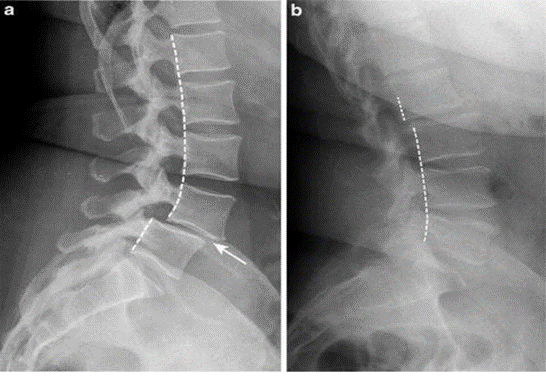

A special X-ray called dynamic x-ray of Lumbar spine reveals instability of the spine. Based on the X-Ray, grade of slip is evaluated.